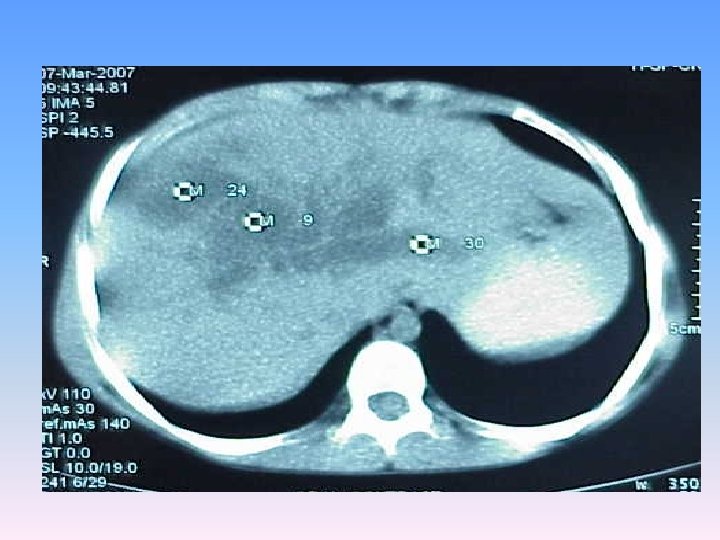

Abdominal CT Scan § A regular lobulated cystic mass in right lobe of liver (120 x 120) without calcification causing dilatation of intra & extra biliary ducts.